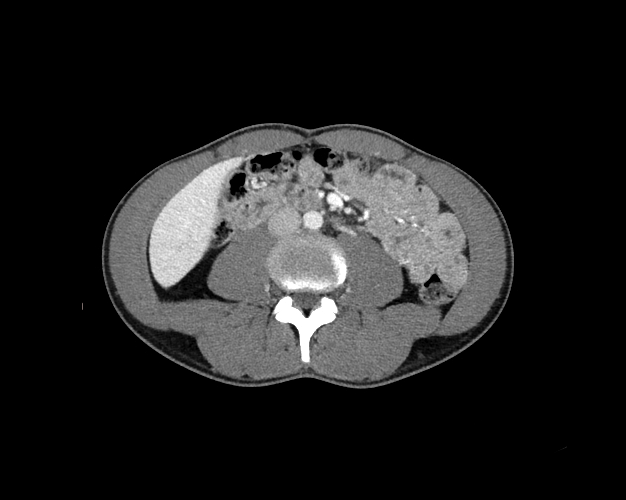

Body

Covers abdominal CT anatomy.